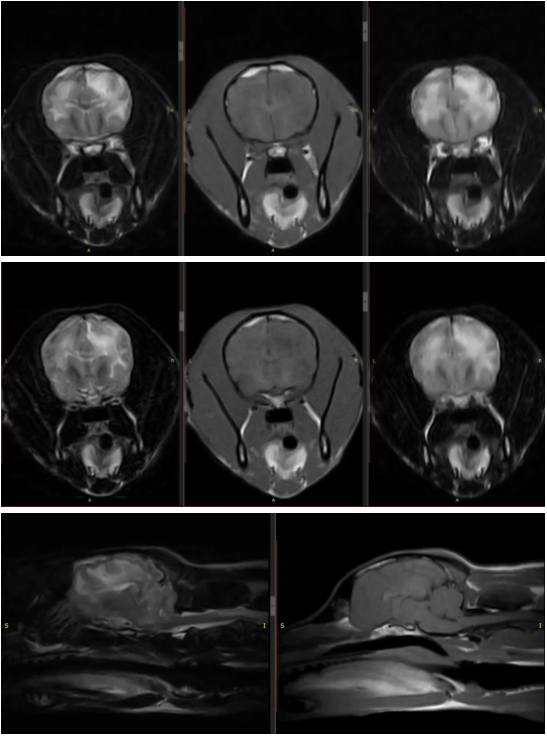

接诊后,尹医生迅速组织全面检查,血液检测提示贫血严重,影像学则发现脾脏存在巨大肿物。面对高龄患犬和复杂病情,他制定了周密的诊疗计划:先输血稳定生命体征,再安排CT血管造影,精准评估肿物与周围组织的关系及是否存在远处转移。CT结果显示,肿物确源于脾脏,并伴有全身多处淋巴结肿大,提示病情已不容拖延。

杨院长凭借丰富的急诊经验,从可视黏膜苍白和腹围增大这两个关键体征,迅速将诊断方向锁定在致命的腹腔内出血(血腹)。急诊超声检查即刻证实了他的判断:肝脏肿大且结构异常,腹腔内充满游离血液。病情危急,猫的生命悬于一线。杨院长当机立断,首先进行紧急输血以稳定生命体征,为后续治疗赢得宝贵窗口。随后,他果断进行剖腹探查手术,切除了已破裂的病变肝叶。